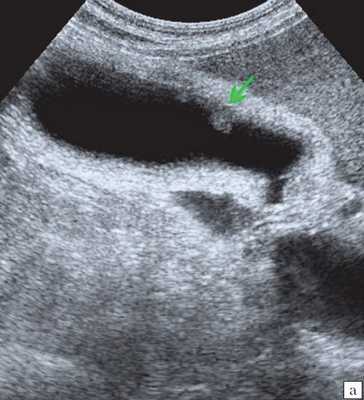

(Слева) На поперечной трансабдоминальной сонограмме в ямке желчного пузыря визуализируется эхогенная структура изогнутой формы с акустической тенью — изменения, характерные для «фарфорового» желчного пузыря.

(Левый) Пример полного кальциноза: у пациентки 67 лет, жалующейся на периодические боли в области желчного пузыря, при сканировании в черно-белом режиме в ямке желчного пузыря определяется тонкая гиперэхогенная полулунная линия, отбрасывающая плотную акустическую тень.

(Правый) У этой же пациентки в той же области в правом верхнем квадранте ожидаемо определяется диффузная криволинейная линия кальциноза, повторяющая контуры желчного пузыря.